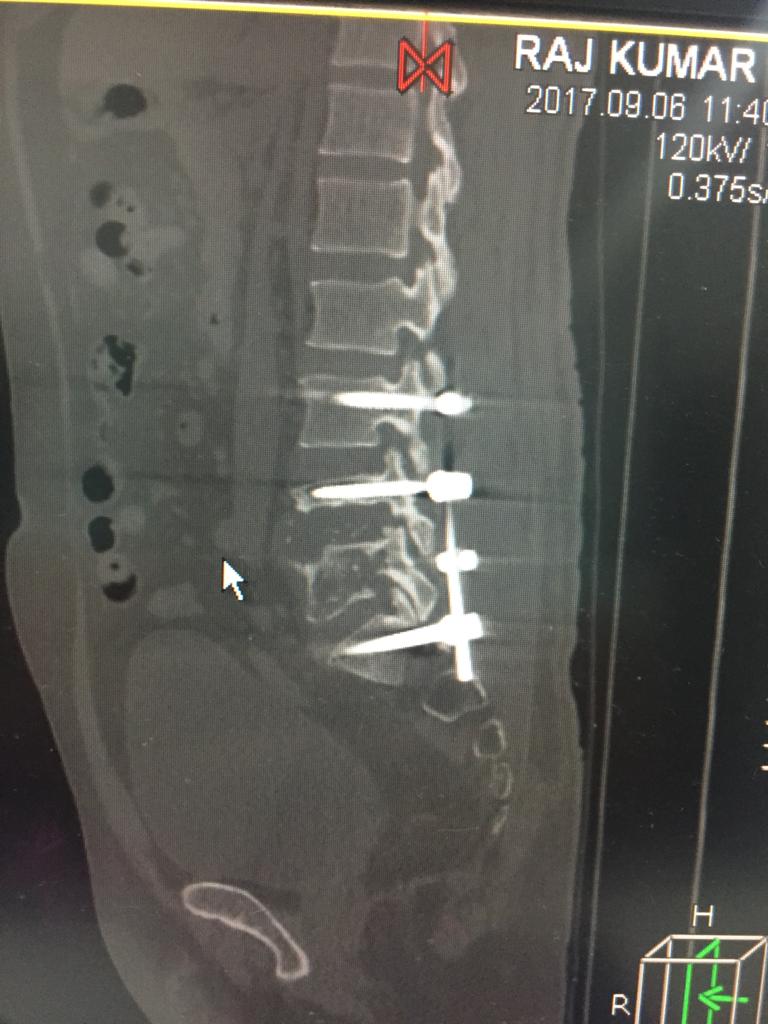

Cases